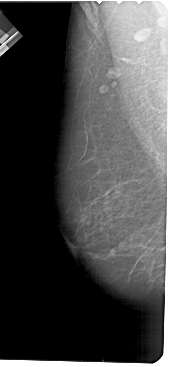

A_1529_1.LEFT_CC

FILE: A_1529_1.RIGHT_CC.OVERLAY

TOTAL_ABNORMALITIES 2

ABNORMALITY 1

LESION_TYPE MASS SHAPE OVAL MARGINS ILL_DEFINED

ASSESSMENT 4

SUBTLETY 4

PATHOLOGY MALIGNANT

ABNORMALITY 2